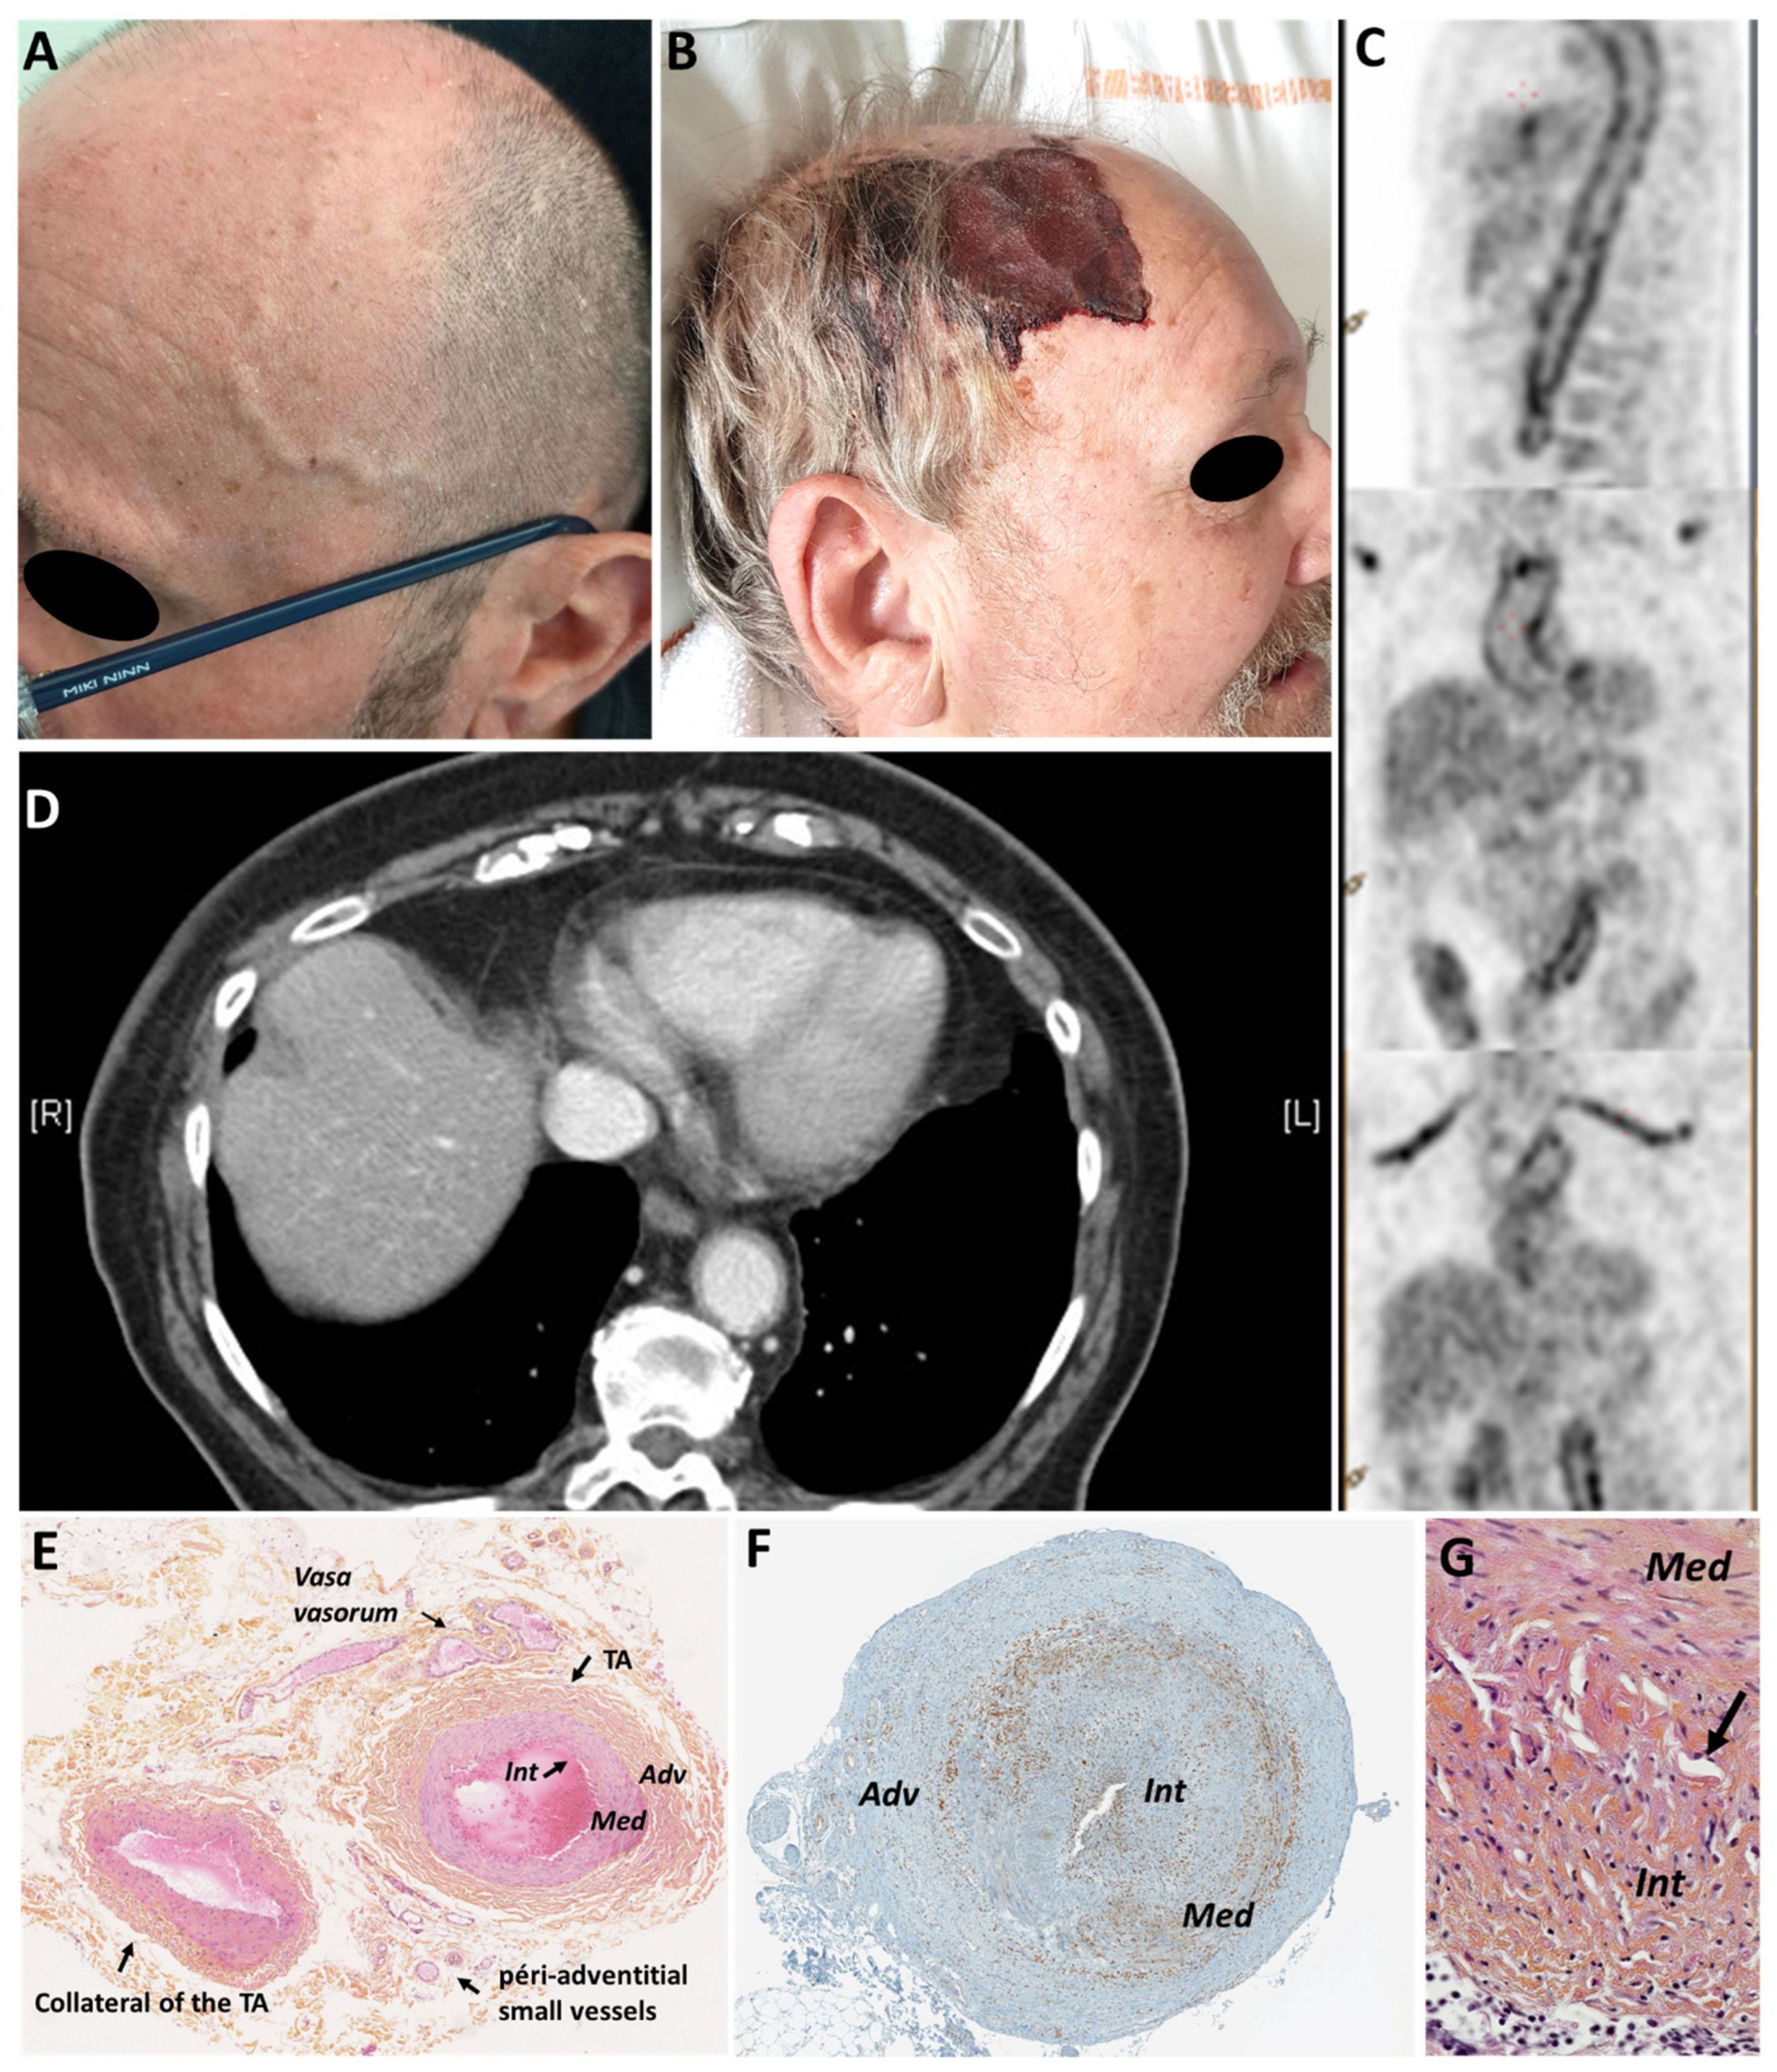

| GCA | Incidence: 14.6 (range: 6.0–43.6) per 100,000 persons aged ≥50 years [73] Prevalence: 75.5 per 100,000 inhabitants (107.8 in women, 40.1 in men) [74] | - Headache, scalp tenderness, or jaw claudication.Abnormal TA exam: induration, tenderness to palpation, edema, decrease/abolition of the temporal pulses - No involvement of the intracerebral vessels. | - PMR - Claudication of a limb - Abolition/decrease of a peripheral pulse - Aortic complication (aneurysm, dissection) - Ischemic complications: Ophthalmological: AAION, CRAO, PION, diplopia Neurological: Stroke (posterior vertebral territory) Myocardial infarction, limb ischemia | - Inflammatory syndrome (95%) - Inflammatory anemia, thrombocytosis (40–50%) | Granulomatous, non-necrotizing panarteritis, inflammatory cellular infiltrate of the media and/or intima made of mononuclear cells, multinuclear giant cells, fragmentation of the internal elastic lamina, destruction of the media, stenosing hyperplasia of the intima | - Glucocorticoids (constant effectiveness except for ischemic sequelae) - 2nd line (relapse(s), corticodependence): tocilizumab, methotrexate |

| Necrotizing vasculitis (AAV and PAN) | PAN: annual incidence = 0.9–8.0 per million in Europe prevalence = 31 per million [73] AAV: Combined incidence annual rate for GPA, MPA and EGPA = 24.7 to 33.0 per million [73] | - Cephalic symptoms in 88% of cases in case of temporal involvement (headache, jaw claudication, scalp tenderness, abolition of the temporal pulse). - Other systemic signs (renal, skin, peripheral neuropathy, ENT...) | - Arthralgia, myalgia - Skin signs (purpura, necrosis, livedo) - ENT signs (rhinitis, sinusitis) - Ophthalmologic signs (vasculitis, exophthalmia, and scleritis in GPA) - peripheral neuropathy (mononeuritis > polyneuritis) - Glomerular nephropathy (AAV) or vascular nephropathy (PAN) - Pachymeningitis (GPA) - Pulmonary signs (asthma (EGPA), nodules (GPA), alveolar hemorrhage (GPA and MPA)) - Heart disease (EGPA) - Digestive signs (perforation, pancreatitis, appendicitis, peritonitis), mainly in PAN | - Inflammatory syndrome - Biological signs related to organ damage - ANCA Anti-PR3: GPA Anti-MPO: EGPA, MPA No ANCA: PAN | Necrotizing vasculitis (fibrinoid necrosis) with cellular infiltrate (T lymphocytes, macrophages, neutrophils, and/or eosinophils): - AAV: small vessels (vasa vasorum or peri-adventitial vessels) without the involvement of the media and intima - PAN: temporal artery and/or its collaterals | - Corticosteroids - Immunosuppressants (rituximab, cyclophosphamide, methotrexate) |